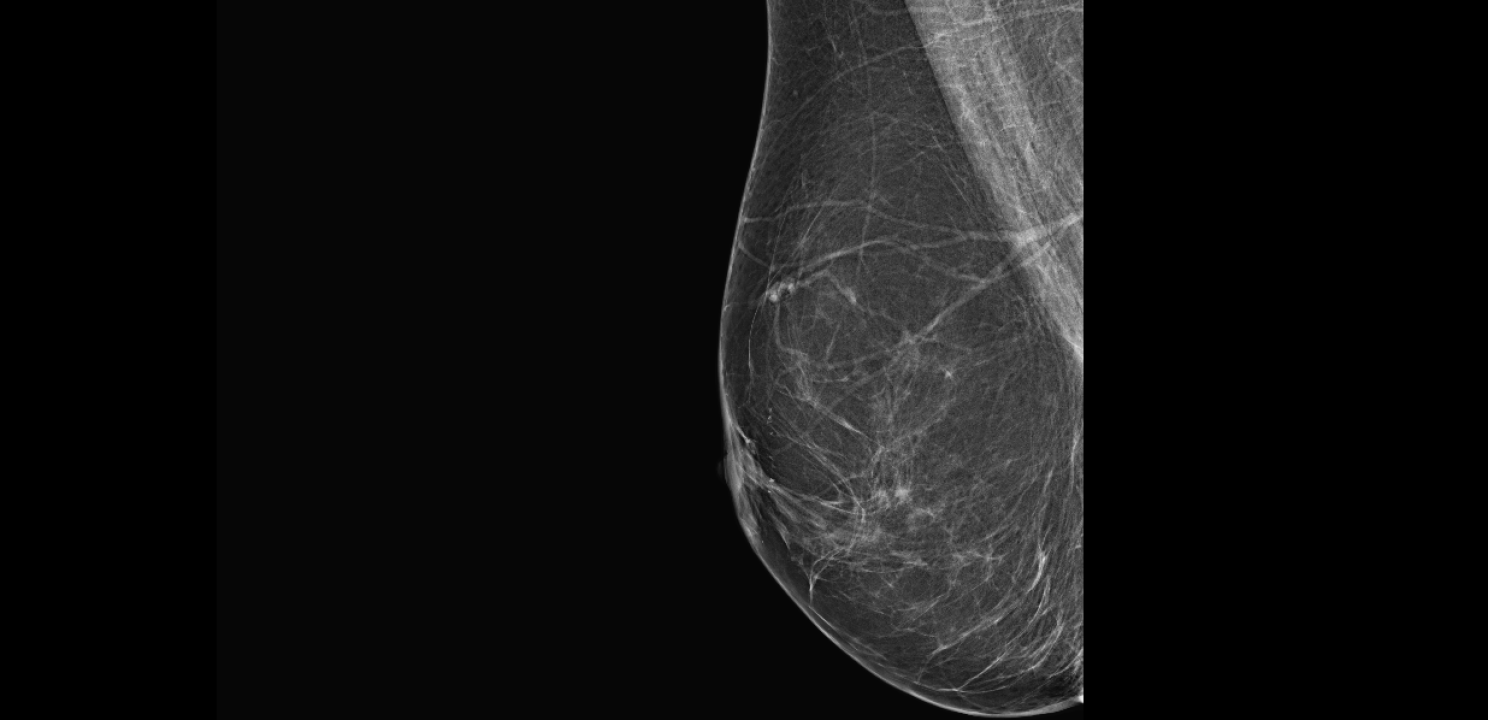

Listopad je mjesec borbe protiv raka dojke, jedne od najčešće dijagnosticiranih zloćudnih bolesti kod žena.